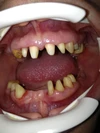

Diş ve Diş eti hastalıkları

Diş Eksikliği

Diş Çürükleri

Diş Eti Kanaması

Kırık Diş

Lezyonlu (Enfekte) Diş

Diş Kırıkları